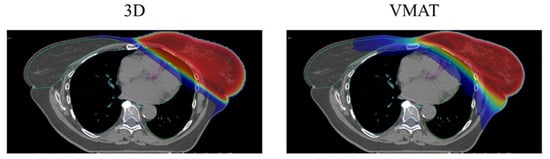

| 3DCRT | 3D conformal radiation therapy |

| VMAT | Volumetric arc modulated radiation therapy |

| Technique of Irradiation | IMRT/VMAT | Better cosmesis and fibrosis compared with 3DRT | Randomized Phase III |